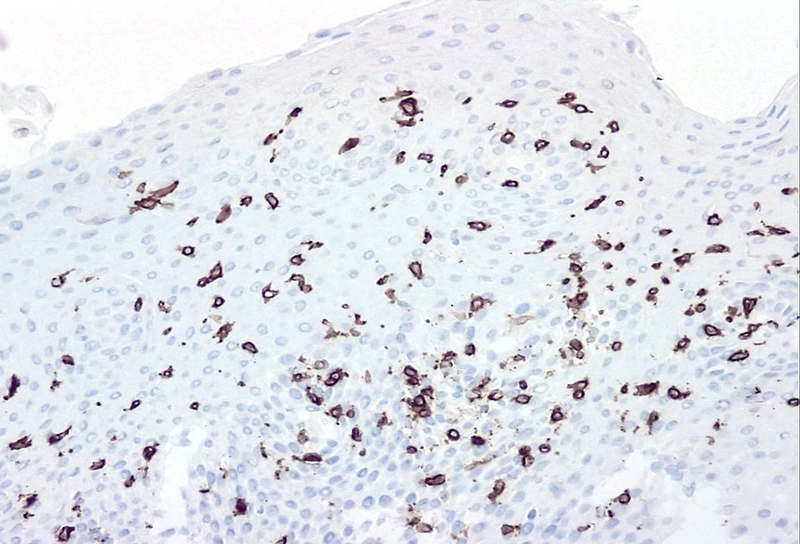

Microscopic examination revealed oesophageal squamous mucosa with an increased number of intraepithelial lymphocytes predominantly clustered around papillae, rare to absent granulocytes, intercellular oedema known as spongiosis and basal cell hyperplasia (Panels A and B). Most of the lymphocytes in the infiltrate were T cells CD3+ (Panel C). CD20 stain shows rare B cells (Panel D). CD4+ T cells outnumber CD8+ T cells (Panels E and F).

There is no standard number of intraepithelial lymphocytes required for diagnosis and studies have included various cut-off values, ranging from 20 to 50 lymphocytes/HPF.  A recently published consensus recommendation by an international expert panel suggests 40 lymphocytes per HPF as cut-off value, following Rubio’s initial criteria for diagnosis. Lymphocytic oesophagitis varies in the prevalence of CD4+ or CD8+ T cells. The predominance of CD4+ intraepithelial lymphocytes appears to be associated with dysphagia, primary oesophageal motility abnormalities and prominent spongiosis.